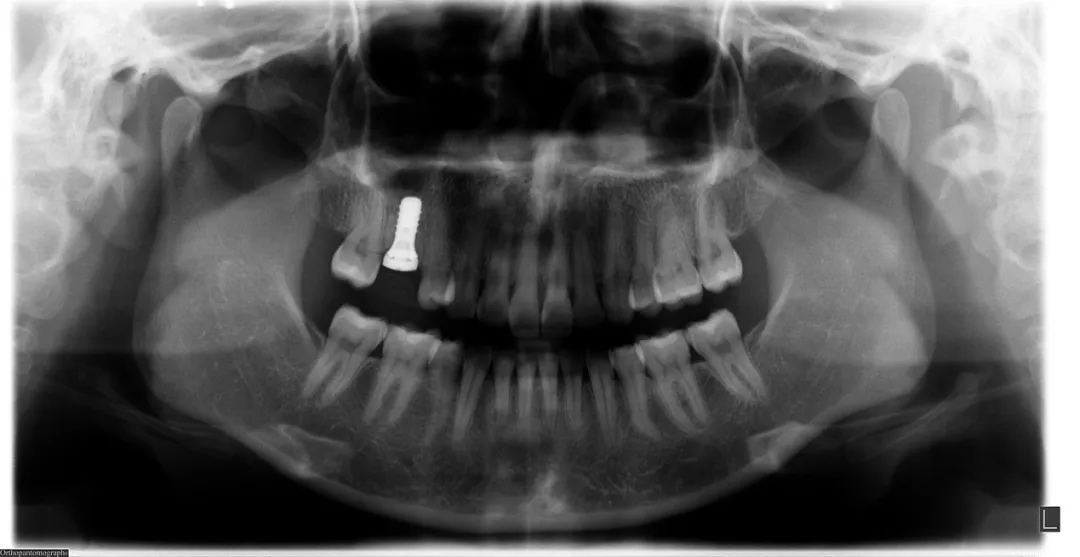

口腔检查:口腔专科检查必不可少。医生会通过口腔X光片、CT等影像检查,精确评估牙槽骨的质量、密度、高度及宽度等情况,以此判断是否适合种植。若牙槽骨骨量不足,可能需要先进行骨增量手术,如骨粉植入,为种植体提供稳固的基础。同时,还会检查口腔卫生状况,若存在牙周炎等问题,需先治疗,确保口腔处于健康状态。

种植手术过程

植入种植体:医生会在牙槽骨上制备一个合适的种植窝,然后将种植体精确植入其中。这一过程需要医生具备丰富的经验和精湛的技术,以保证种植体的位置、角度和深度符合要求。种植体就如同人工牙根,植入后会与牙槽骨紧密结合,为后期的牙冠修复提供稳定支撑。